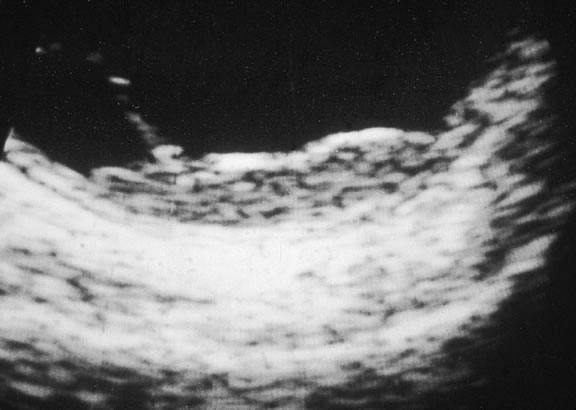

Ultrasonography can support the diagnosis of ciliary body or choroidal melanoma and is a particularly helpful way of disclosing tumors in eyes with opaque media.54 Ultrasonographic studies can alsodemonstrate areas of extrascleral extension. A scan ultrasonography shows a high internal spike and low internal reflectivity. B scan ultrasonography shows characteristic acoustic hollowness and choroidal excavation (Fig. 23). Hemangiomas and metastases usually appear acoustically solid because they contain multiple acoustic interfaces.

Fig. 23. B-scan ultrasound, choroidal melanoma.